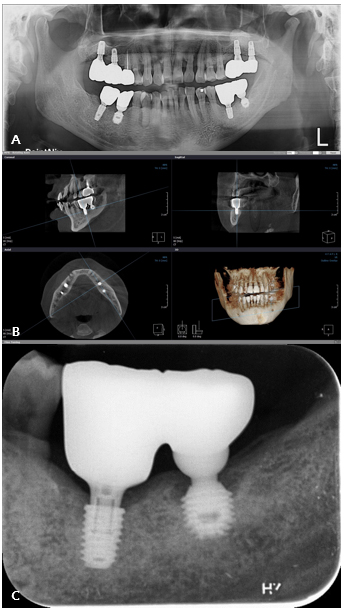

A 57-year-old male presented with suppuration and discomfort in the left mandibular molar region. Clinical and radiographic examinations revealed severe peri-implant inflammation and associated bone resorption around the fixture at site #36, while the implant at site 37 demonstrated stable peri-implant bone support.5 The two implants were restored with a splinted crown prosthesis (Fig. 1).

No documentation regarding the implants was available; therefore, the KAOMI implant finder service was consulted. The system identified the type of fixtures as Bicon implants (Bicon LLC; Boston, MA, USA). Based on this information, the manufacturer was contacted, and an appropriate abutment for #37 the fixture, intended for salvage, was procured (Fig. 2).

After a healing period of approximately 5 months, a new implant (TSIII, 4.5 mm diameter, 7 mm length; Osstem Implant, Busan, Republic of Korea) was placed at site #36 with an initial torque of 25 Ncm. A healing abutment (95 mm diameter, 7 mm height) was placed simultaneously (Fig. 3).

Approximately 3 months after implant placement of #36 implant, prosthetic rehabilitation was initiated. A custom abutment was fabricated for #36, and a new abutment was delivered for the salvaged, preexisting fixture of implant #37 (Figs. 4 and 5).

After 2.5 years, the prosthesis remained functional without significant complications, and radiographs confirmed stable peri-implant bone levels surrounding both fixtures (Fig. 6).